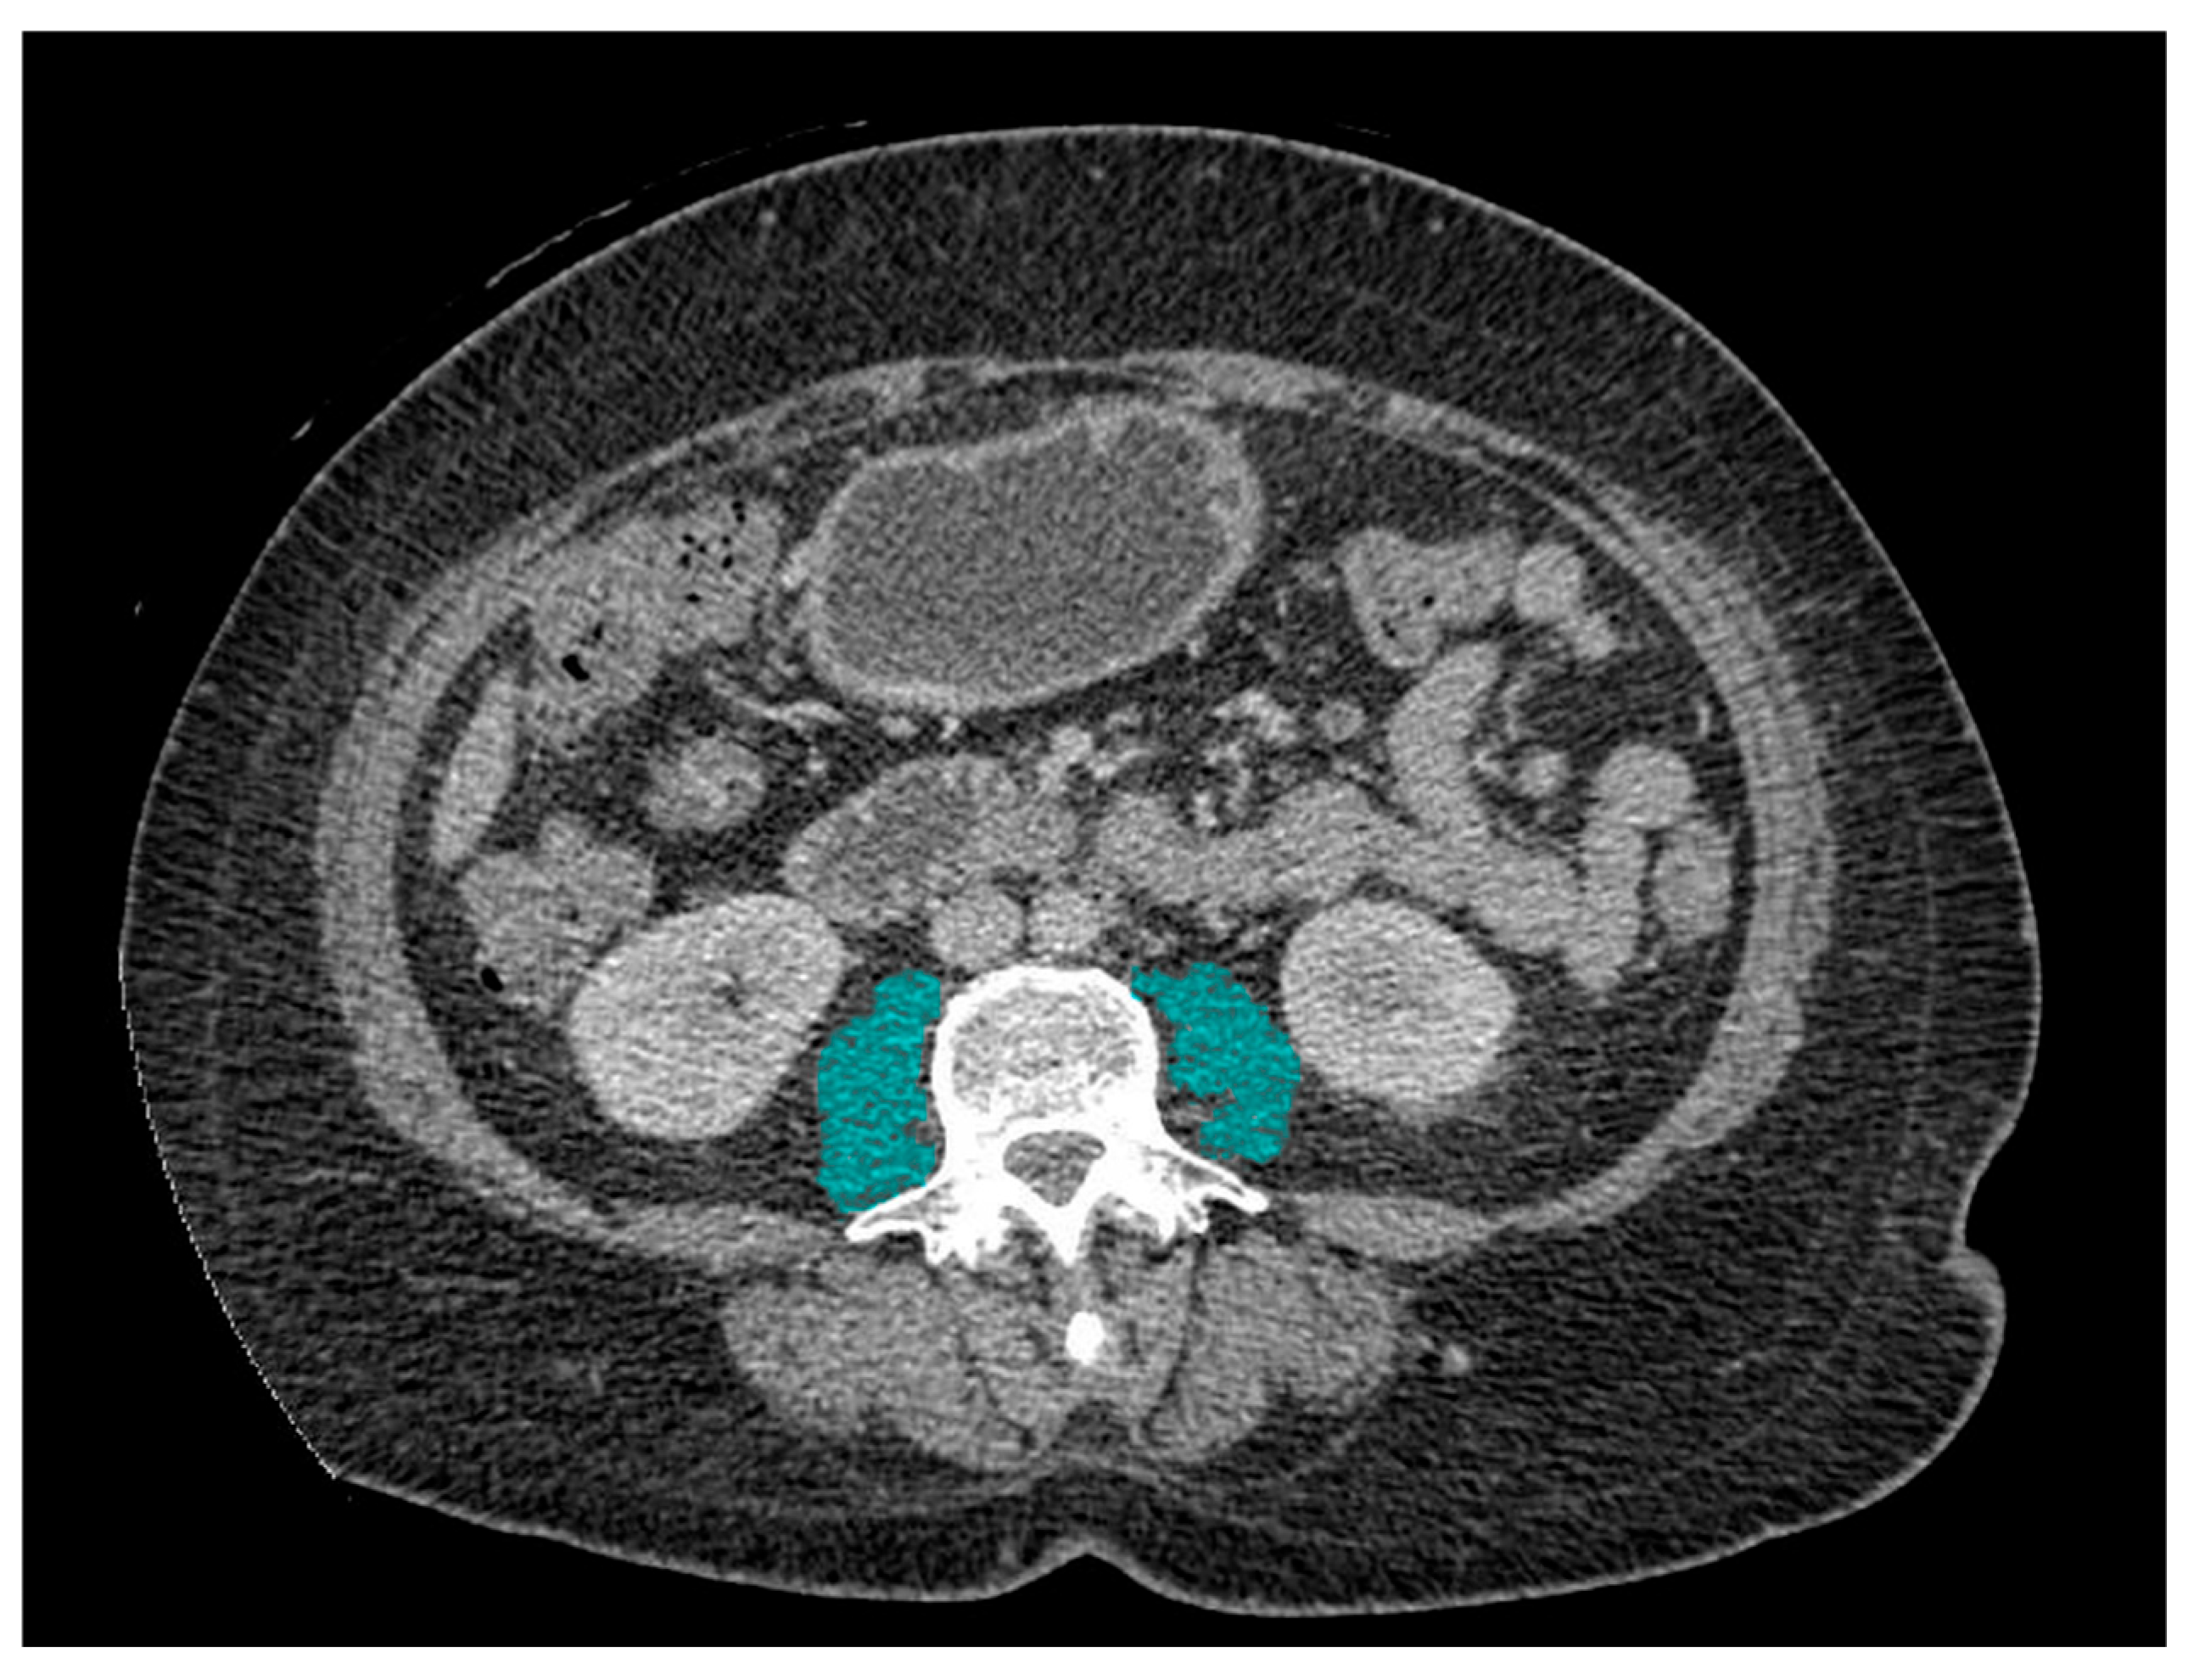

Pre-interventional CT scans were accessed using eRAD PACS Viewer Version 7. PMI was obtained by measuring the cross-sectional area of bilateral psoas muscles at the level of L3 (Figure 1). PMI was calculated as the psoas muscle area divided by the squared patient height in units of cm2/m2. Presently, there is no consensus regarding optimal PMI cutoff values for sarcopenia, which vary in different populations [16]. In this study, sarcopenia was defined as the lowest sex-specific quartile PMI at pre-interventional CT scan, in accordance with what was performed in previous studies [16,17,18,19].

Figure 1.

Representative CT imaging of the psoas muscle. Axial CT slice at the level of L3 showing bilateral psoas muscles (blue shading) used to calculate the PMI.